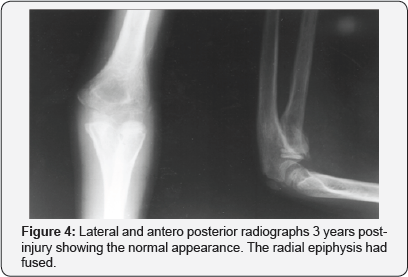

Under general anaesthesia, a great degree of instability of the medial ligamentous structures was noticed. Closed reduction of the dislocation was attempted, but was partially successful (Figures 2A & 2B). Subsequently, through a lateral incision, an open reduction of the dislocation was performed. The head of the radius was also reduced and fixed with a Kirschner-wire (Figure 3). The arm was splinted in a long cast with the elbow at 90° of flexion. The cast and the K-wire were removed 3 weeks later and active movements of the elbow begun. At 6 months the proximal radial epiphysis had fused with marked callus formation. Three years after the injury, the range of extension / flexion was 5°/160° and supination / pronation was 50°/55° and the elbow was stable (Figure 4).